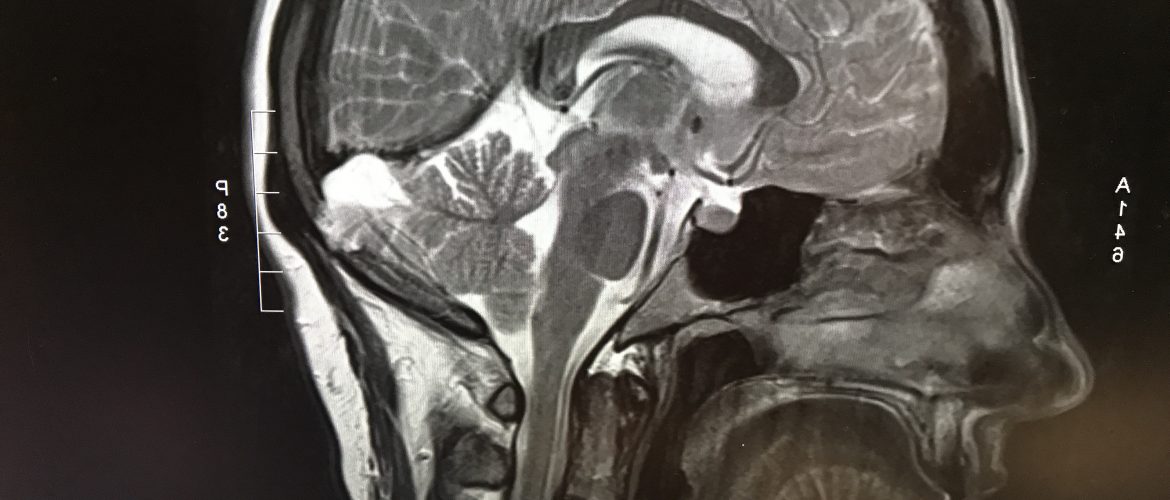

J’ai pu ramener le CD avec moi, et le regarder tout de suite… j’ai failli ne pas le faire. Mais j’ai assez de tête sur les épaules pour savoir que je n’ai pas les connaissances pour tout comprendre, donc je ne m’affolais de rien de ce que je voyais, je pouvais juste tenter de reconnaître les structures et m’émerveiller de la beauté des images.

En attendant, mon endocrinologue a voulu avoir les images de l’IRM de juillet pour faire faire une 2e analyse (un 2e avis, quoi), afin de confirmer qu’il n’y avait rien d’anormal en juillet… ce qui ne voudrait malheureusement pas dire qu’il n’y a rien d’anormal maintenant.